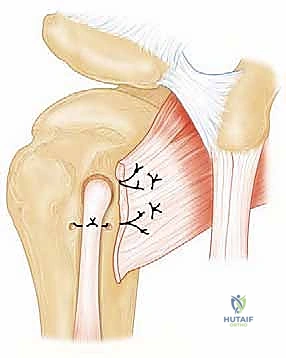

5. الخطوة الثالثة: إصلاح تمزق العضلة تحت الكتف (Subscapularis Repair)

هذه هي الخطوة الأساسية والأكثر دقة:

* تنظيف وتجهيز العظم: يتم تنظيف منطقة ارتكاز الوتر على عظم العضد (الحديبة الصغيرة) لإزالة الأنسجة الندبية وكشف العظم الحي، مما يحفز تدفق الدم ويساعد على التئام الوتر بالعظم لاحقاً.

* تحرير الوتر: إذا كان الوتر متراجعاً ومتقلصاً للداخل، يقوم الجراح بتحريره بلطف من الأنسجة المحيطة لضمان عودته إلى مكانه الطبيعي دون شد مفرط.

* وضع الخطاطيف (Suture Anchors): يقوم الدكتور هطيف بزرع خطاطيف جراحية دقيقة (مسامير صغيرة جداً محملة بخيوط طبية فائقة القوة) في العظم.

* خياطة الوتر: يتم تمرير هذه الخيوط عبر نسيج الوتر الممزق باستخدام أدوات دقيقة.

* العقد والتثبيت: يتم عقد الخيوط بإحكام لسحب الوتر وربطه بقوة بسطح العظم، مما يعيد التشريح الطبيعي للكتف.